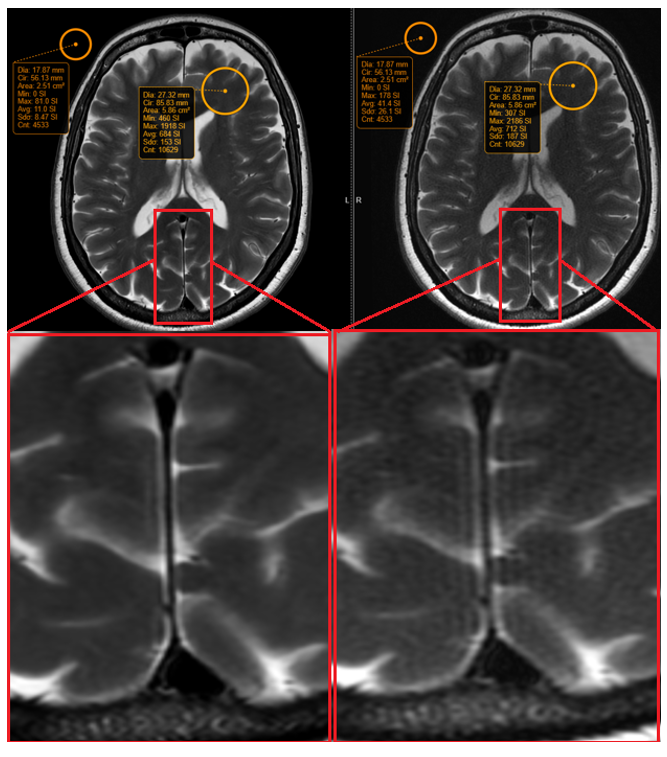

Figure 1 displays representative brain images of a thin-slice coronal T2 weighted fast spin echo pulse sequence, which was acquired with a small field of view of 14 cm. The image quality improved with DL-based reconstruction, and upon signal measurements, a 354% increase in SNR was noted.

Figure 1. 2 mm coronal T2 weighted fast spin echo pulse sequence, with a small field of view of 14 cm. SNR gains of 354% were noted when the image was reconstructed through the DL-based reconstruction pipeline (left) compared to the conventional pipeline (right).